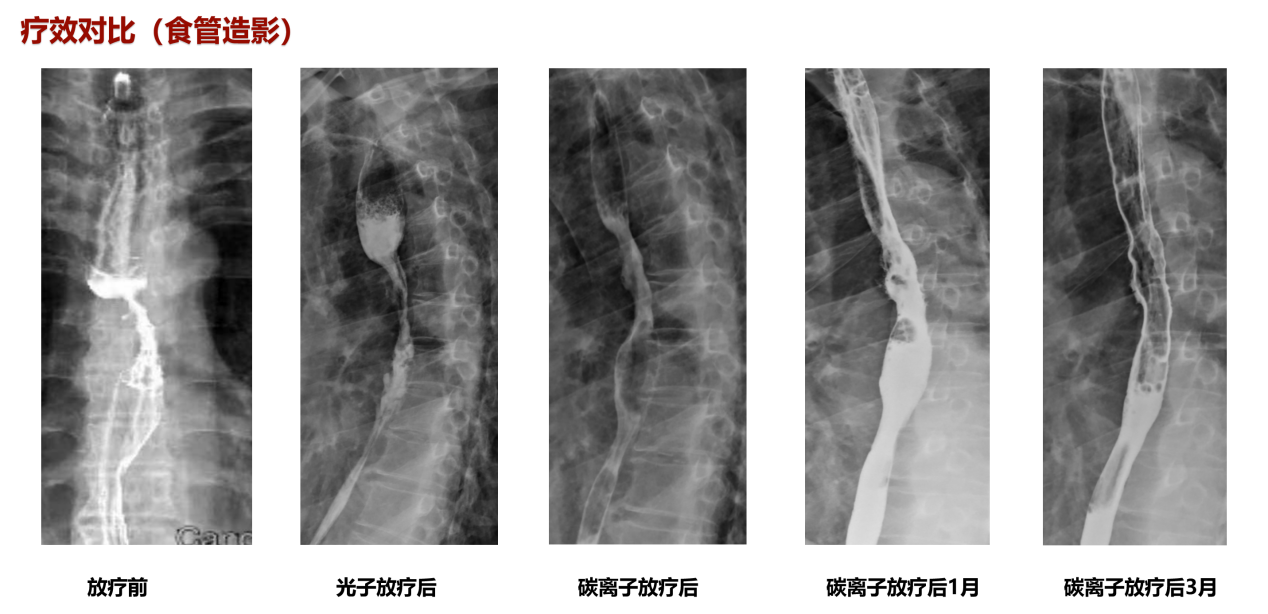

患者苏某某,男,73岁。2022年2月患者无明显诱因出现进食不畅,进行性加重。查上消化道造影示:食管中段癌(髓质型)。胃镜示:食管距门齿26cm可见向腔内环周生长的肿物,表面溃疡、糜烂、质脆易出血。镜下活检后病理示:(食管)鳞状细胞癌。诊断:1、食管恶性肿瘤(中段 髓质型 鳞状细胞癌 cT3N2M0 III期 KPS评分: 90分 2、冠状动脉硬化性心脏病(心脏支架置入术后)。治疗计划:同步放化疗【1、放疗(光子+碳离子),2、化疗:卡培他滨单药口服化疗】。放疗剂量:光子VMAT技术PTV2 2Gy×20F=40Gy,碳离子PTV1 4Gy(RBE)×4F,总56Gy。

该患者放疗后进食哽噎较前明显好转,放疗后复查胸部CT提示:现胸中下段食管管壁增厚并强化、管腔变窄,病变局部与邻近结构分界不清,较前食管病变明显好转,临床疗效评价为PR。放疗3月后复查食管造影提示管壁通畅,行胃镜检查并取检未查见癌细胞,疗效评价为CR。【病例提供医生:李小军 科室:放疗中心一科(兰州院区)】